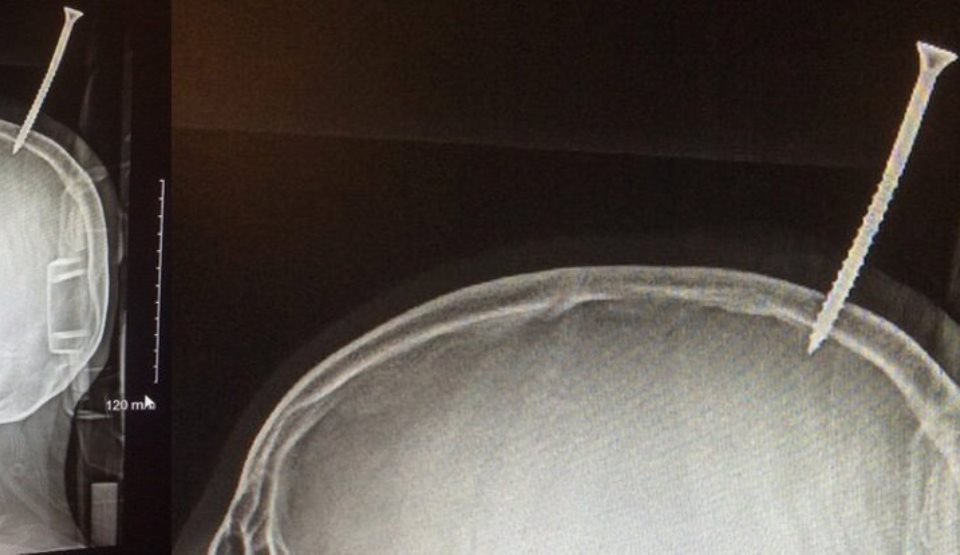

Deşi nu se pune problema ca donarea unui rinichi să îţi scurteze viaţa sau să crească riscul de boli de inimă sau diabet, un nou studiu (publicat la final de ianuarie în Annals of Internal Medicine) spune că poate creşte riscul altor probleme de sănătate. Dr. Emanuele Di Angelantonio, autorul studiului şi directorul Institutului Naţional pentru Cercetarea Sănătăţii Donatorilor de la Universitatea Cambridge din Anglia, spune că există un risc mic, dar real, pentru cei care donează un rinichi.

Studiile anterioare care au avut în vedere peste 100.000 de donatori au arătat că aceştia au avut un crisc crescut de tensiune arterial, iar la femei s-au adăugat şi un risc de creştere a complicaţiilor legate de sarcină, precum pre-eclampsia.

Dr. Di Angelantonio a cercetat peste 52 de studii deja publicate comparând peste 118.400 de donatori în viaţă  şi 117.600 de oameni care nu erau donatori pentru a evalua riscurile de sănătate  pe termen mediu şi lung associate denarii unui organ.

Donatorii de rinichi  au avut o presiune sanguină diastolică mai mare şi un risc mai mare pentru o boală de rinichi în fază terminală, însă, în afară de acestea, profilul riscurilor erau comparabile cu ale persoanelor care nu donaseră niciun rinichi. Nu a existat nicio dovadă că donatorii ar avea un risc mai mare de deces, boli cardiovasculare, diabet de tip 2 sau o calitate a vieţii mai redusă.